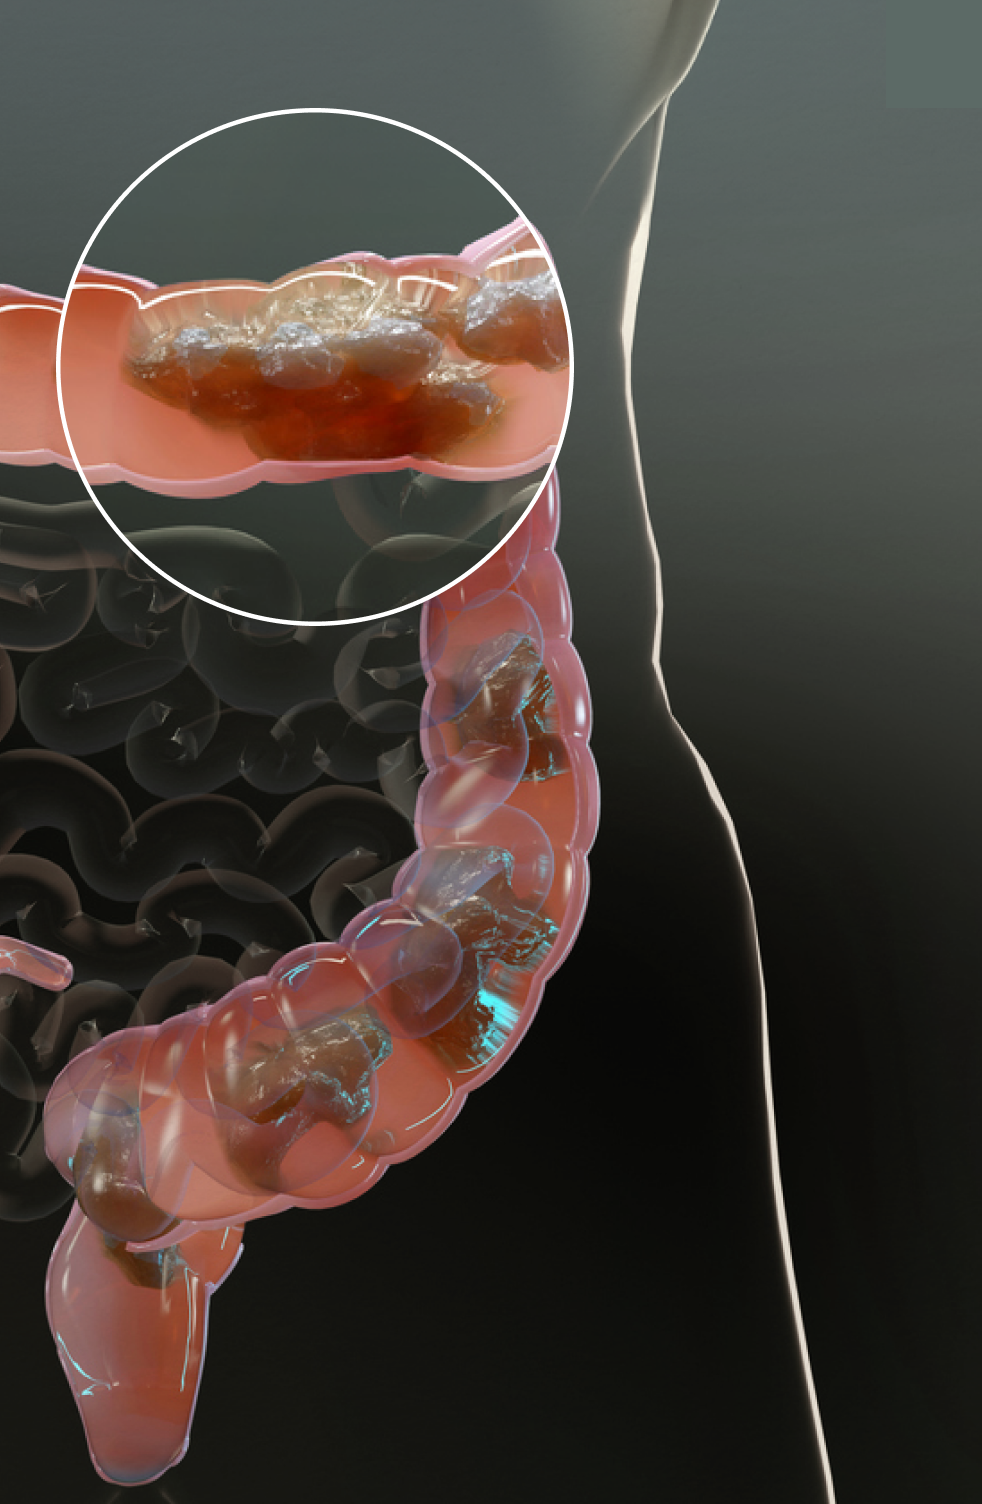

Elimipure targets fecal plaque to get your system back on track.

Fecal plaque,a hardened accumulation of waste material, toxins, and harmful bacteria that adheres to the walls of the colon over time, is an often overlooked cause of digestive troubles. Fecal plaque buildup can obstruct proper nutrient absorption and create a breeding ground for harmful bacteria, paving the way for digestive issues such as constipation, bloating, discomfort, and unexpected weight gain. It can further act as a physical barrier, obstructing the passage of stool.

Elimipure focuses on breaking down and eliminating the fecal plaque buildup responsible for compromising the integrity of the colon. Our formula contains potent natural ingredients that work synergistically to soften and dissolve hardened waste material, clearing the path for smoother digestion, regular bowel function, and better overall health.